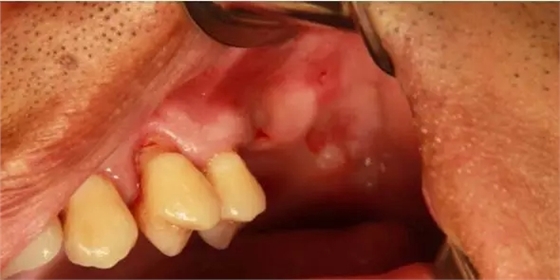

患者50歲,男性,身體健康。左上6,7缺失,骨高度2mm。

術(shù)前口內(nèi)照和CT片。